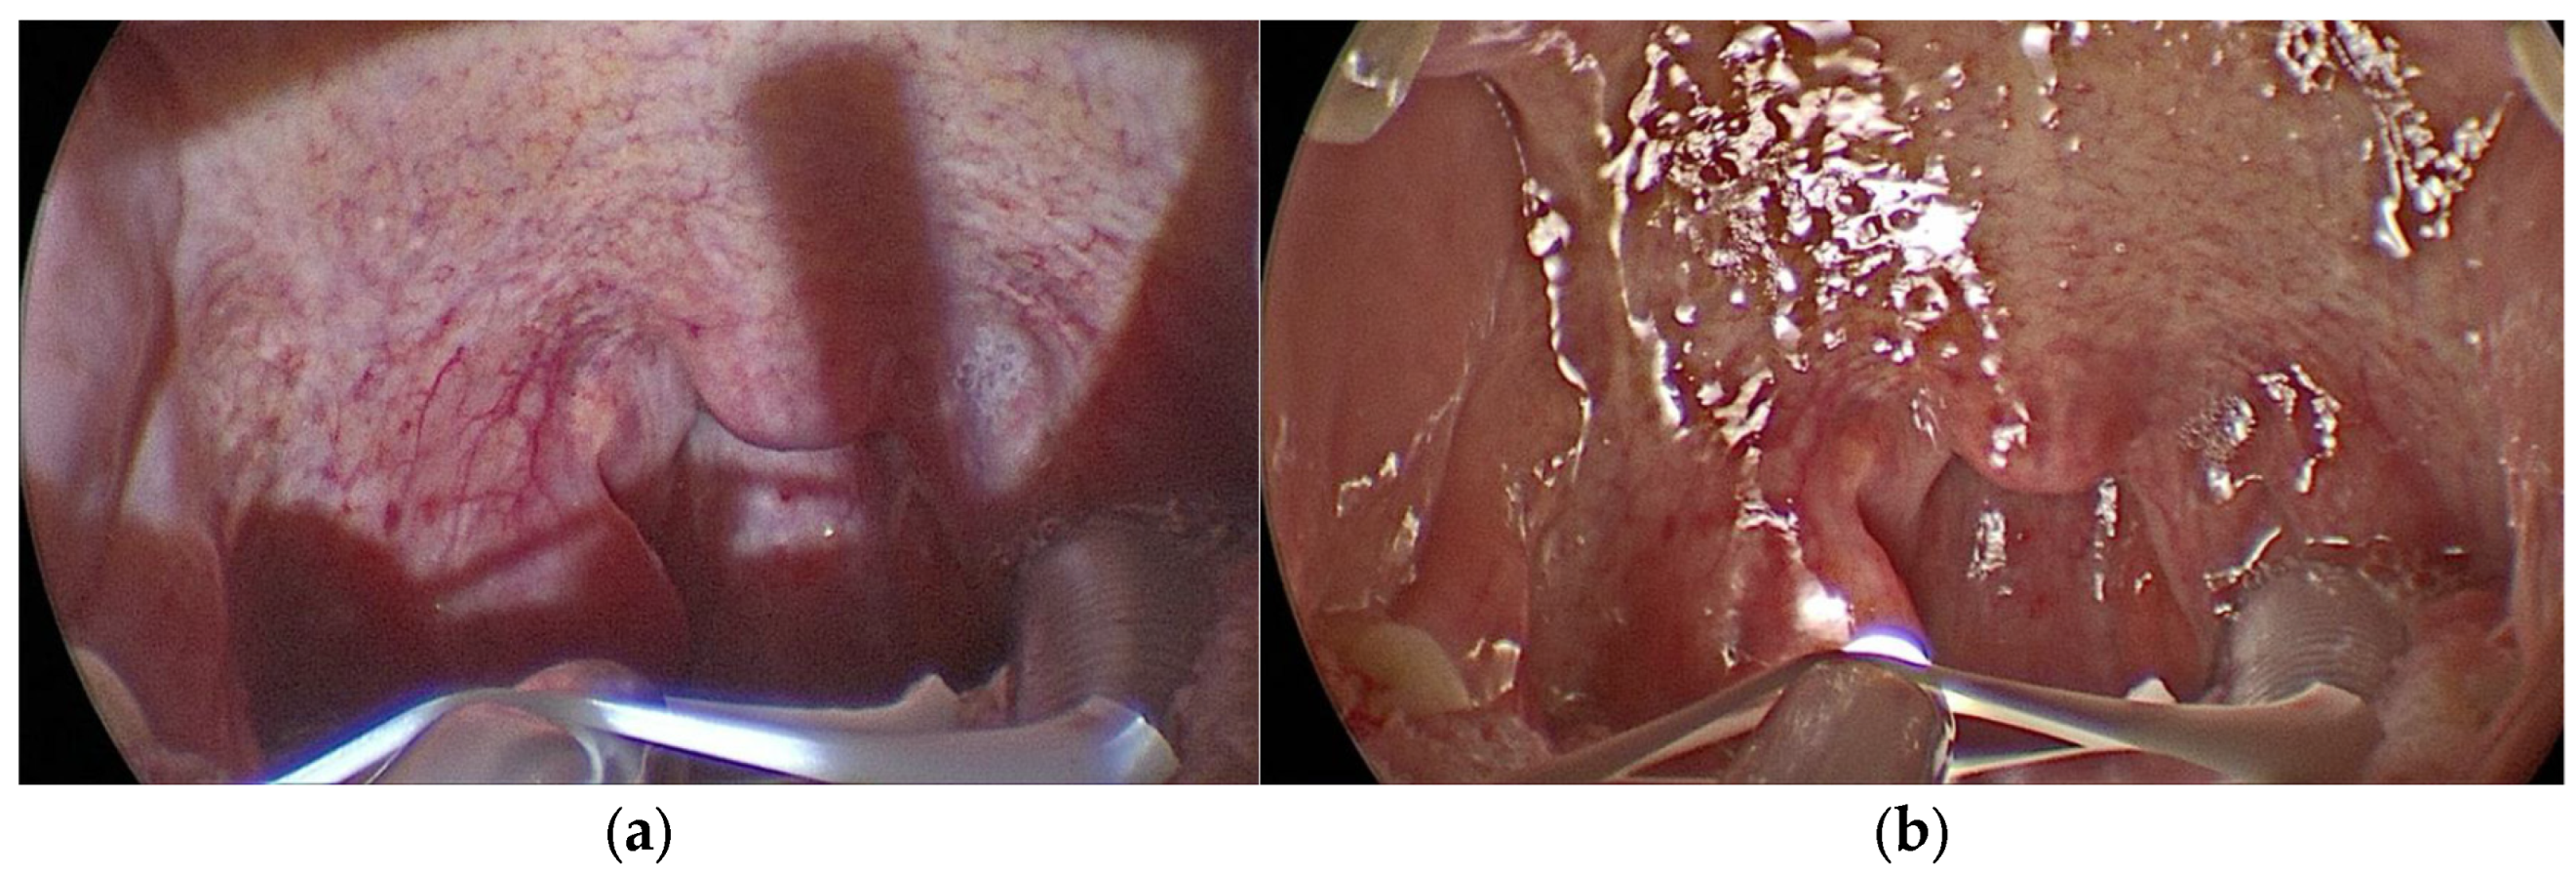

On each patient, the procedure was performed by an expert surgeon: on one half of the palate with the headlamp and the other half with KLAROTM illumination system; the residents attended the surgical procedures, which were filmed with a 70° rigid endoscope and transmitted on the screen (Figure 3a,b).

Figure 3.

(a) Oropharynx lighting with headlamp; (b) oropharynx lighting with KLAROTM.

The quality of visualization on the screen was statistically significantly better with KLAROTM versus the headlamp to identify the fibers of the palatopharyngeal muscle and to recognize the entrance and exit point of the sutures and the needle tip (Table 2). The uniformity of vision and the absence of shadows on the screen during the use of KLAROTM made the image more uniform and enjoyable (Figure 3a,b). Also, the residents did not report significant differences for the visualization of the posterior pharyngeal wall and uvula.